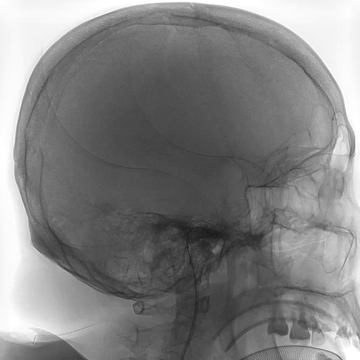

Tubridge Plus Case 4